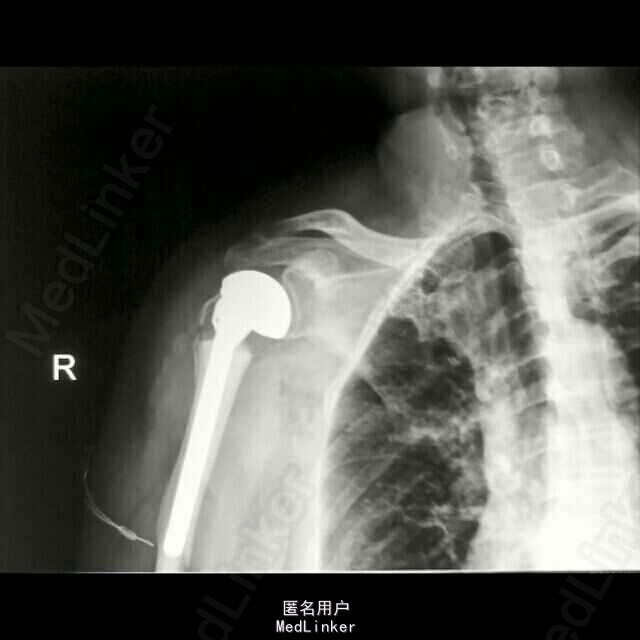

诊断:1、右侧人工肱骨头置换术后伴假体周围骨折 2、慢性肺气肿伴左侧胸腔积液 3、双侧脑基底节区陈旧性腔隙性脑梗塞灶 4、血压病(2级 高危层) 5、骨质疏松症(重度) 6、右髋关节置换术后 治疗: 因患者高龄,基础疾病较多,较重,故手术风险大,经呼吸内科,心血管内科及神经内科会诊及治疗处理后,患者内科病情控制稳定,予行手术治疗,术中检查,右肩关节假体无松动,故单纯予行假体周围骨折固定术治疗。

随访:术后1周指导患者功能锻炼,术后1月患肢功能基本恢复正常。讨论:患者系人工肩关节假体周围骨折,骨折远近段髓腔内填充有骨水泥,骨折端髓腔血运中断,故保守治疗效果欠佳,容易发生骨折多次移位,复位及固定困难,容易并发骨折延迟愈合,甚至不愈合,故应考虑积极手术治疗,早其有效固定骨折,并行局部植骨,有利于骨折生长及愈合;同时因患者右肱骨髓腔内骨水泥及金属假体填充,钻孔困难,钢板螺丝钉内固定术难度较大;同时不排除假体松动可能,故根据患者病情及具体情况,拟定手术方案:1、若假体松动,则行关节翻修,予更换加长柄假体,同时骨折部位记忆合金环抱器内固定;2、若术中假体无松动,则直接行“假体周围骨折切开复位记忆合金环抱器内固定术。